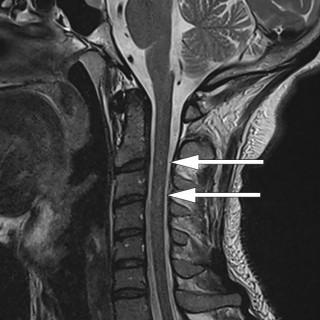

En mann i 50-årene ble innlagt etter residiverende episoder med brystsmerter. På innleggelsesdagen synkoperte han fra sittende stilling. Utredningsforløpet avdekket en diagnose som er sjelden, men med klassiske symptomer og funn. En mann i 50-årene med kjent hypertensjon, velregulert med kandesartan (tabletter, 8 mg × 1), ble henvist til akuttmottaket på grunn av episoder med brystsmerter. Han var normalvektig, hadde aldri røykt og hadde ingen rusbrukslidelse, og det var ingen kjent diabetes, hyperkolesterolemi, opphopning av hjertesykdom eller prematur hjertedød i familien. Over en periode på...